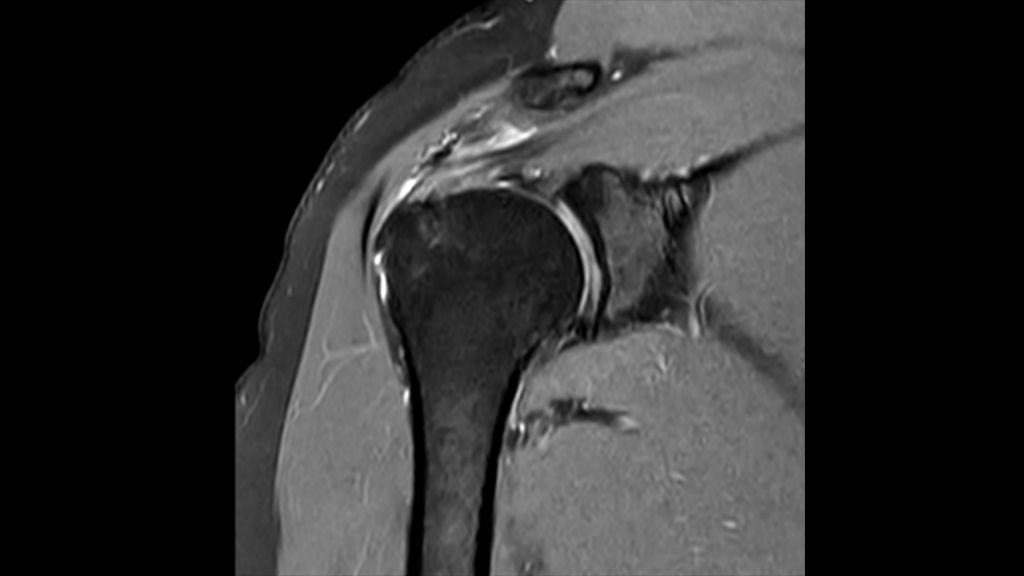

This innovative 1.5T MRI system is powered by Philips exclusive BlueSeal magnet for helium-free operations. And it incorporates a wealth of AI²-driven technologies to simplify and automate the most complex clinical and operational tasks. So you can focus on what matters the most: your patients.

This breakthrough solution is designed to help boost MR productivity, speed up exams, empower clinicians to make informed clinical decisions, and control the costs of MR imaging.